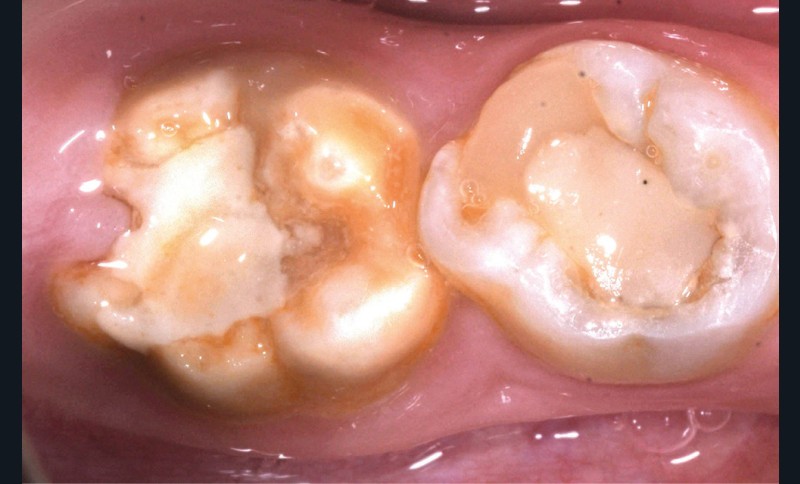

Une patiente de 10 ans se présente en consultation. Aucun antécédent médical ou chirurgical n’est constaté. À l’examen clinique, nous observons une forme sévère de MIH sur 36 et 46 avec des fractures post-éruptives [1] (fig. 1a et b). En raison de cette pathologie, la patiente se plaint de sensibilités spontanées sur ces dents, ayant un impact sur sa qualité de vie, et une maîtrise difficile de l’hygiène bucco-dentaire. Les secteurs antérieurs maxillaires et mandibulaires présentent aussi des opacités délimitées entraînant une gêne esthétique conséquente pour la patiente.